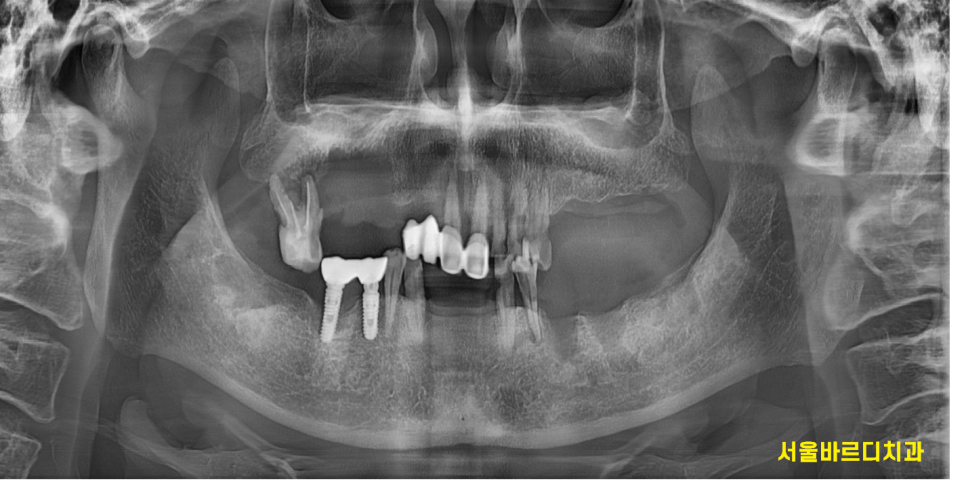

많은 치아가 상실되었고

남아 있는 치아도 썩.. 상태가 좋지않아

이를 뽑아야하는 상태입니다.

230725

치아는 치태와 치석으로 덮여있어

깨끗하게 청소 후 재평가가 필요하고..

1차적으로 전반적인 잇몸 발적

빨갛게 부어오른 잇몸과

고름이 나오는 치아들

염증이 빠져나올 길이 없어 풍선처럼 부푼 잇몸도 관찰됩니다.